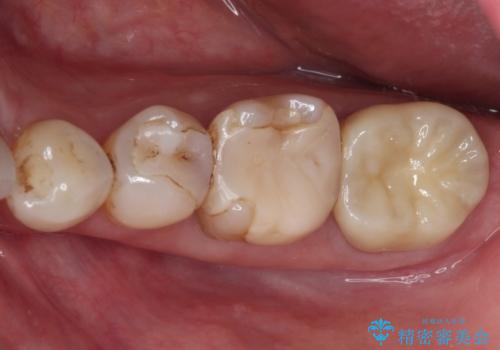

仮歯を装着した時点でものが挟まる症状は改善されました。

根管治療により咬合時の違和感も解消されました。